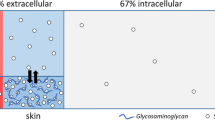

Although it was first suggested by Russian investigators in the 1970s [18], the concept of tissue Na+ was more fully developed by Jens Titze and co-workers over the last 20 years. In keeping with previous evidence of positive Na+ balance without commensurate water retention or body weight increases in subjects on short-term high salt diet [19], they reported a dissociation between Na+ and weight changes in unique long-term (months) observational [20] and interventional [21] studies, thus supporting the idea of a body reservoir for non-osmotic water-free sodium storage. Rat body-composition studies [14, 22–24] and 23Na-magnetic resonance imaging (MRI) in humans [16] pointed to the skin, and to some extent the muscle, as the specific depots for excess Na+ accumulation, with the negatively charged glycosaminoglycans (GAGs) network serving as the dynamically regulated substrate for putative interstitial skin Na+ binding [25].

The above conclusions on osmotic and non-osmotic interstitial Na+ may appear conflicting. Moreover, how does the proposed non-osmotic interstitial Na+ elude parallel water accrual while simultaneously driving TonEBP-mediated signalling? Notably, our recent body-composition study in SS and SR rats failed to confirm any hypertonic tissue Na+ accumulation [30••]. While tissue Na+ content and concentration did increase with high-salt diet, the findings were interpreted in light of a whole-tissue histochemical deductive approach [31,32,33] and appeared in keeping with a prediction model based on the extracellular-to-intracellular composition of tissues [34•]. In hypertensive patients, as in rats, skin Na+ excess was isotonic; tissue water, Na+ and Na+/K+ ratio were associated with pulse pressure, BNP, and, independent of any other covariate, with age [30••]. Consistently, a close correlation between human skin Na+ and water had already been independently reported [35]. Overall, the conclusions are that (#3) tissue Na+ excess is systemic and reflects extracellular volume (ECV) expansion compared to the intracellular (ICV), with or without an oedematous component. In fact, even the seminal studies reported that excess Na+ accumulation was accompanied by reduced ICV [23].